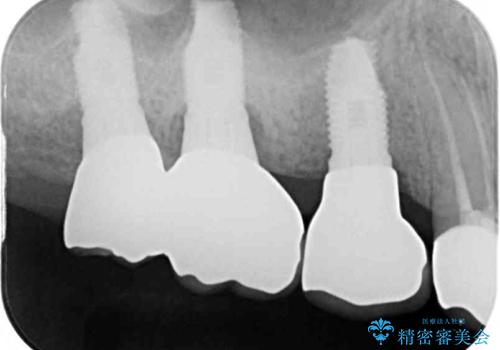

折れてしまった歯 インプラントによる補綴治療

- 咬合力により歯が割れてしまった方のインプラント治療です。

抜歯後4ヶ月ほど待ち、後方のインプラントと同一メーカーのインプラントを埋入することとしました。